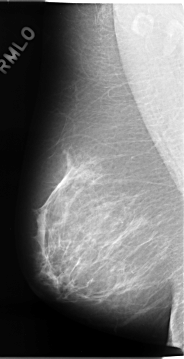

C_0075_1.LEFT_MLO

LEFT_MLO LINES 4648 PIXELS_PER_LINE 2416 BITS_PER_PIXEL 12 RESOLUTION 50 OVERLAY